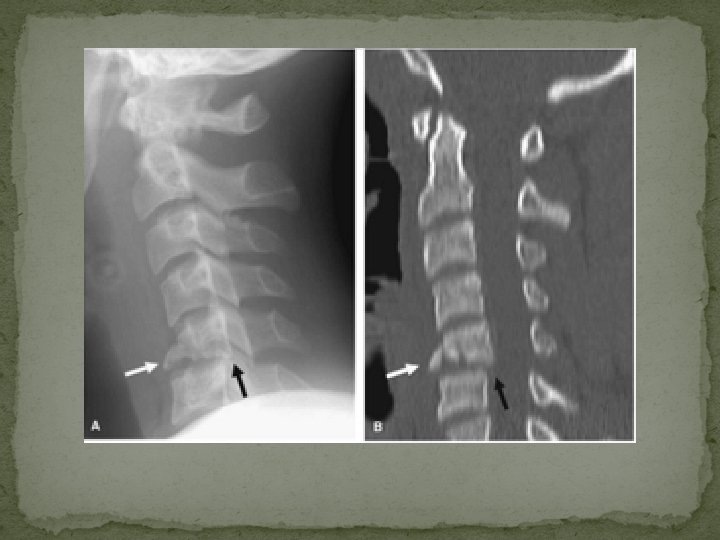

Hyperextension teardrop fracture

Hyperextension injuries �most often encountered in elderly patients with severe spondylosis or with spinal ankylosis from other etiologies �Mechanism - In hyperextension fracture dislocation the posterior spinal elements experience impaction forces, producing loading fractures of the posterior vertebral body, laminae, spinous process, or pedicles �Characteristically, the spine above the level of injury is posteriorly displaced (retrolisthesis), the intervertebral disc space is widened anteriorly and narrowed posteriorly and the facet joints are disrupted